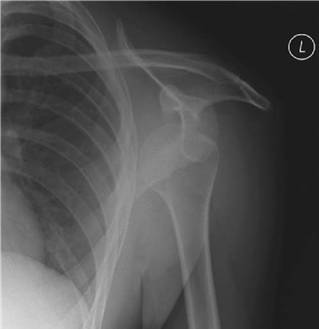

What condition is illustrated here?

Avascular necrosis of the femoral head with segmental collapse.

Can you describe any classifi cation systems for this condition? What stage is shown in the radiographs above?

There are many classifi cation systems described for osteonecrosis of the hip. The Ficat and Arlet (1980) system describes X-ray appearances and is one of the most simple to use:

Stage 1: no bony changes seen on plain X-ray

Stage 2: sclerotic and cystic changes within the femoral head

Stage 3: subchondral collapse and distortion of the femoral head

Stage 4: secondary osteoarthritis with decreased joint space and articular collapse

T he radiographs show Ficat and Arlet stage 4 changes. There is distortion and collapse of the femoral head. The lateral view illustrates the โ€˜crescent signโ€™ associated with subchondral collapse.